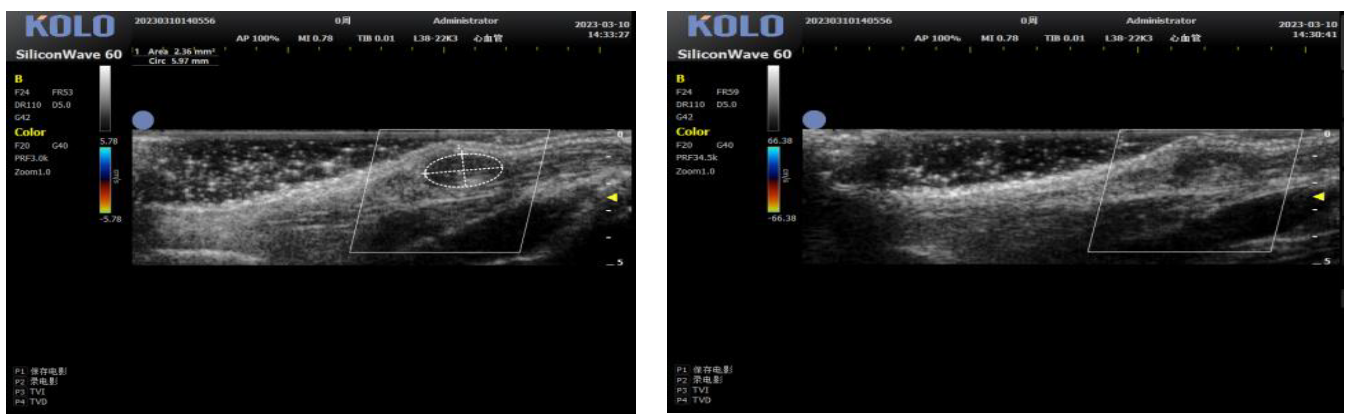

基于全球领先的CMUT 半导体超声技术,集成多项发明专利,珂纳医疗精心研发出 SiliconWave 60 超高频小动物超声成像系统。该系统微米级的超高清分辨率,8-62 MHz 超宽频段和丰富灵敏的彩色多普勒功能为临床前科研用户观察小动物的心血管、腹部脏 器、浅表组织及胚胎等提供了清晰多彩的超声图像。系统的实时无创操作也为科研实验 的反复验证,长期动态观察等提供了极大的便利性。

3.1 腹主动脉(长+短轴+管壁距离测量+血流流速)

3.2 颈动脉(长轴)